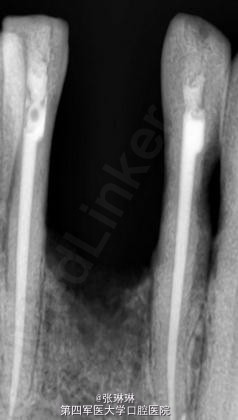

根据龋坏程度、患者的症状、修复需要,且对收费及牙髓处理均征得同意后第一次行右下4、5,左下4、5、6;第二次行左下2,右下2 ,右上7一次性根管治疗术, 术后见右下4,左下4均有侧支充填,且位置对称,左下6近中根中部有侧支;左下5、左下6远中根管均多个开口。 热牙胶垂直加压后有封闭剂和牙胶超填,但无术后反应。